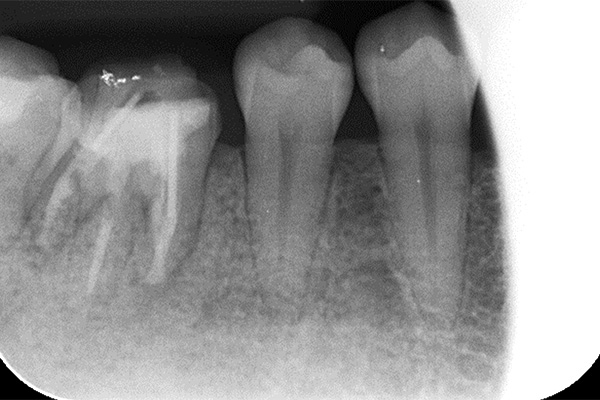

①自覚症状なし・歯肉にサイナストラクト(排膿路)あり

②初診時レントゲン解説

・歯根周囲に透過像(黒い影)あり

・遠心根根管充填:アンダー

根管治療そのものは、2回で終了し、水酸化カルシウム貼薬し経過観察(患者様希望のため)

約2か月後、根尖透過像の縮小を確認し根管充填(MTA使用)。

レントゲン解説:4根管すべてに根管充填が密にされていることを確認できる

透過像は消失し、明らかな骨形成を認める。(黒い影の消失)